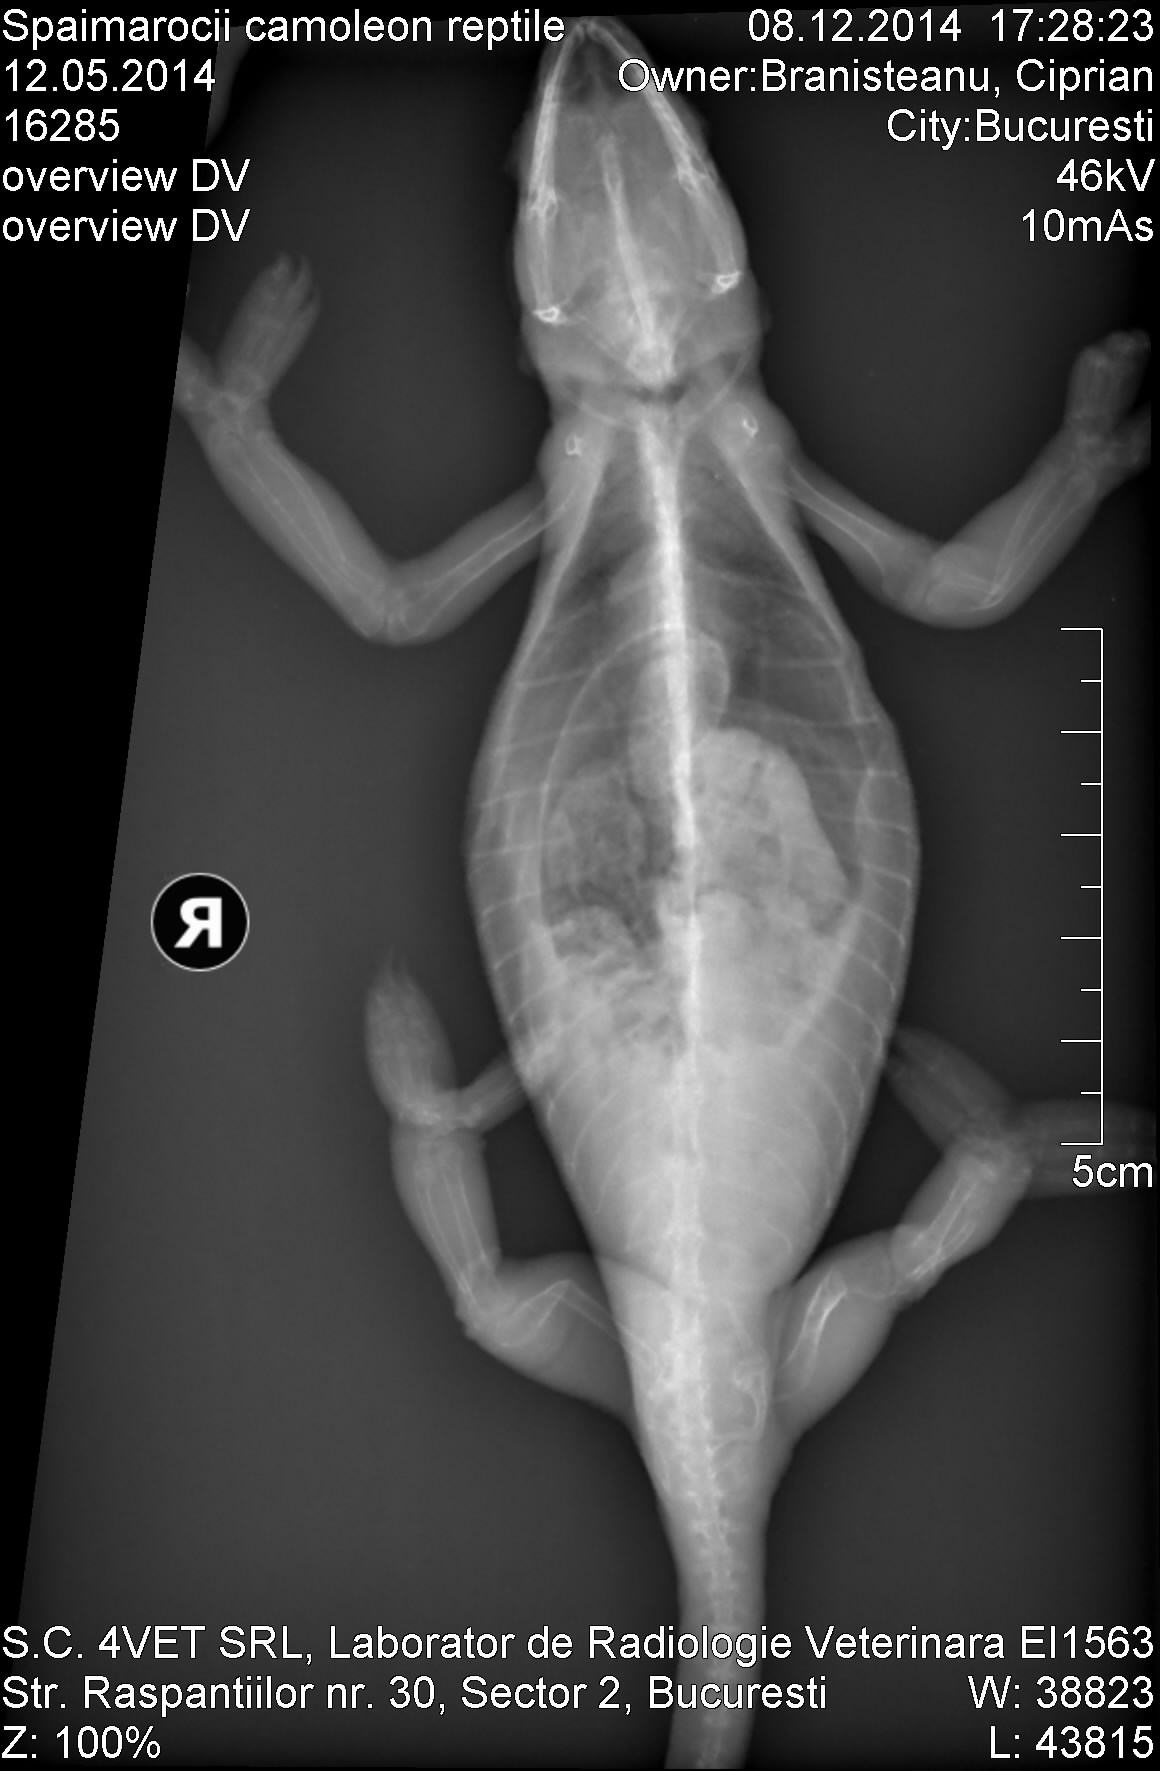

I was with my chameleon to the vet today, he made hem a radiograpy that I attach here. The vet told me the methabolic problem is mostly from missing radiation of the sun in tha cage. Looks like the chameleon have a lot of fractures. I want to take care of hem and make hem well and do whatever it takes for that, I will post info pics here regularity, help for this is very much apreciated.

The vet did some calcium injections to the fracture bone zones, give me some calcium pills that are used to the cats, and told me I should put one pill everyday inside the circket or worm before he will eat it. Then I should come back in 10 days to make hem another injections. What do you think about?

Poor little thing. You can see the fractures in the xrays. Calcium injections are good. Please take him back in ten days as recommended by the vet.

Do you have a light that emits UVB (ultraviolet light)? You should have two different kind of lights - one for heat only (basking) and a UVB light to mimic the sun. This is help your chameleon produce Vitamin D (we call it D3), which is produced naturally by the body and is required to absorb calcium. Calcium without D3 is not going to fix your chameleon, but you have to be careful not to overdose on D3. You need a UVB light immediately; chameleons cannot live without one.

I was looking at the Xray and I saw so many fractures, in one place a bone was snapped at a 90 degree angle (back left leg, what would be the femur in humans not sure if it's the same for chams), is it even possible for this girl to recover and live a healthy life?